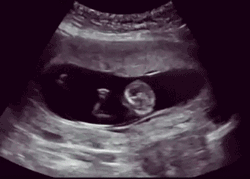

经新生儿科医生仔细检查后,发现该婴儿只有6个月左右,体重1.1公斤,属于早产儿,并且心跳微弱。

B超:利用B超可以确认胚胎是否着床,着床位置是否正确,还可以看出胚胎大小与判断预产期。